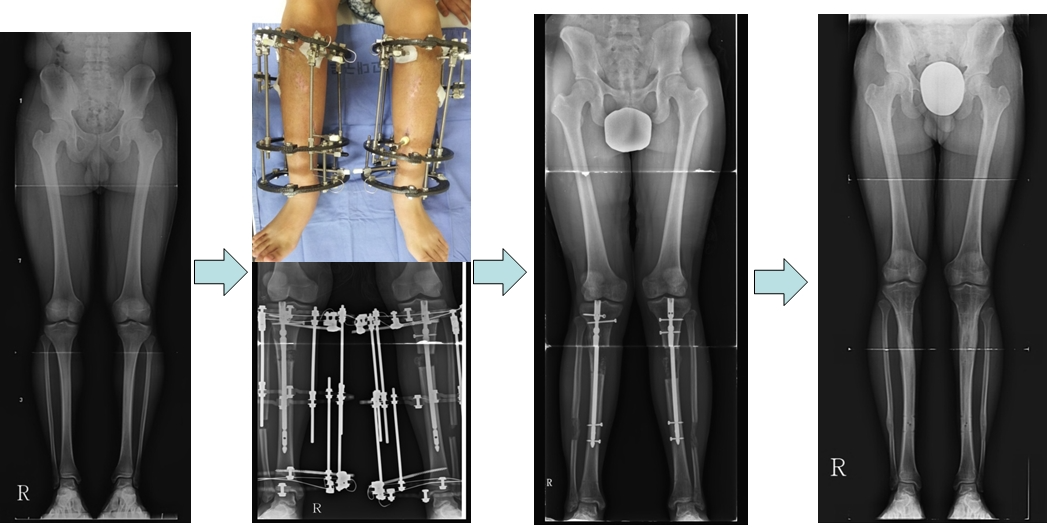

공지 저신장증에서 하지연장관리자-다른 질병없이 키가작은 환자가 종아리길이를 연장하여 10센티정도 길어진 모습입니다. A short patient without any disease. Height was increased about 10 cm by lengthening tibia. 다음글공지 한쪽다리 짧은환자에서 허벅지뼈 연장이전글공지 연골무형성증환자의 하지연장목록